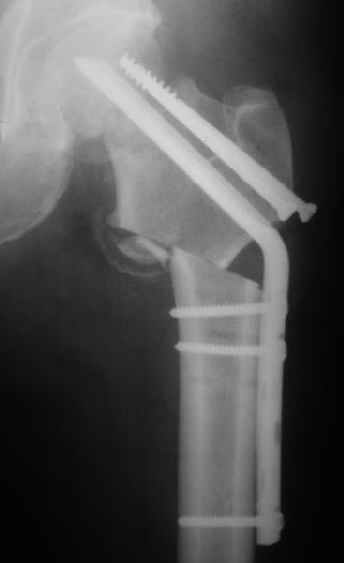

Мужчину 56 лет оперировали у нас в августе 2003 г. - вальгизируюшая остеотомия из-за позднего (через 2 мес. после травмы) поступления с переломом шейки бедра (картинки 1,2). Курильщик, соматической патологии не было. Сейчас поступил с жалобами на проблемы в области тазобедренного сустава, на снимках 3,4 видно вырезывание клинка.

A male 56 years old was operated in Aug 2003 - valgus osteotomy performed because of delayed admission with neck fracture (2 months) images 1,2. Smoker, no other major medical problem.